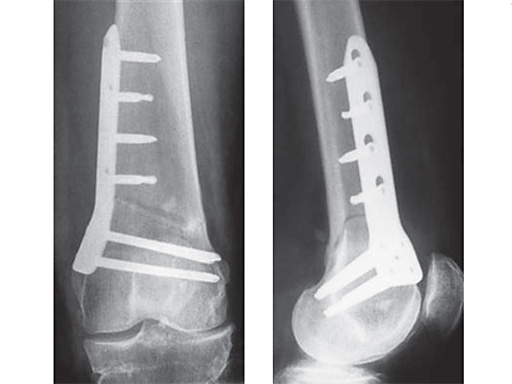

27-year-old male developed severe lateral joint line pain after lateral menicectomy.

Case provided by Philipp Lobenhoffer, Hannover, DE

An anteromedial skin incision is used. This skin incision can be reused and expanded during subsequent knee surgery. The vastus medialis muscle is dissected from the septum, the medial patellofemoral ligament (MPFL) and the distal insertion of the vastus medialis muscle are partially incised. Two blunt Hohmann retractors are placed around the distal femur. The oblique osteotomy starts in the medial supracondylar area and ends in the lateral condyle, approximately 10 mm inside the lateral cortex. For guiding the closing wedge osteotomy of the distal femur a specific saw guide will be available soon. Alternatively, it is possible to use K-wires inserted under image intensifier control to mark the bone cuts. The saw cuts are made with retractors protecting the soft tissue and vessels. The wedge is removed and the height and depth of the osteotomy can be measured. At this time it is possible to make modifications concerning the wedge size. Closing the wedge must be done gradually by gentle compression of the lower leg laterally, and stabilizing the knee joint medially near the area of osteotomy. This may take several minutes to enable plastic deformation of the lateral cortex to close the osteotomy gap. Leg alignment is checked radiologically after closing with a rigid alignment bar positioned between hip and ankle center. The bar representing the weight-bearing line should pass the preoperatively defined mechanical axis. The plate is inserted from distal under the vastus medialis muscle. The distal drill holes are oriented in a 20 angle inclination on the frontal plane to avoid a posterior perforation of locking head screws in the distal femur. The distal four bolts are placed. A lag screw is positioned in the dynamic hole directly above the osteotomy for compression of the osteotomy site. The screw should be tightened carefully using the image intensifier. The plate is now fixed to the shaft with bolts monocortically, and the lag screw is replaced by a bolt bicortically. The wound is closed in layers after insertion of a drain. The patient is mobilized on the first day after surgery. Partial weight bearing is recommended for 6 weeks, active movement of the knee is enhanced. Biomechanical testing confirmed superior stability of medial closing wedge techniques as compared to lateral open wedge techniques and favourable axial and torsional loading characteristics of the TomoFix medial distal femur (MDF) plate. The plate is now available, as well as a booklet on the operative technique.